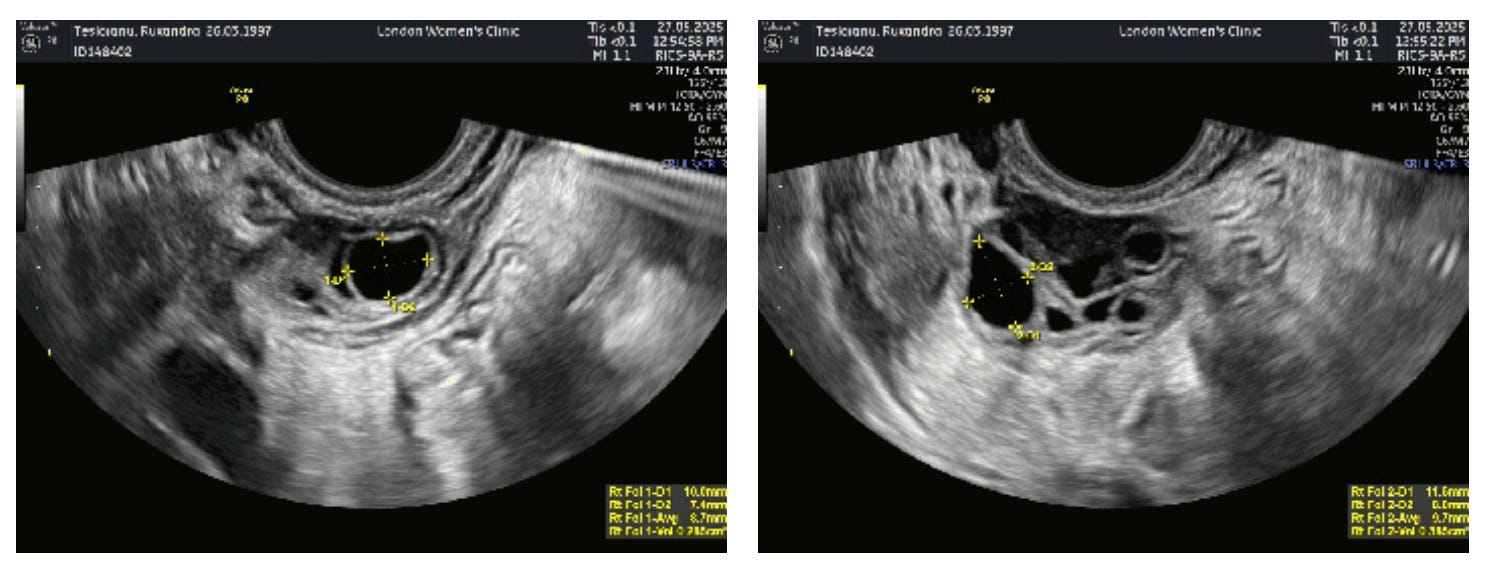

“Oh my god, do you have many eggs!”. “Is that good?” I asked, momentarily forgetting everything I had read about all this. “Yes, yes it is”. She then started to count. Right ovary: 26. Left ovary: 24. There might have been more of them, but at some point I could tell she was bored and gave up counting. I had at least 50 eggs in my ovaries in total. In scientific terms, that was my antral follicle count (AFC). This was good. Phenomenal even — the average for my age is something around 15. I could not quite believe it though, so I asked again: “no abnormality?”. The nurse shook her head. A consultation with the doctor afterwards confirmed what the nurse said.

The so-called “cysts” in my ovary were no cysts at all. They were antral follicles. On the ultrasound above, they are the black holes in the centre of the image. And the opposite of anomalous growths: they are seeds of life. And, like many women with PCOS, I had many of them, although 50 is high even for PCOS. That was good. It felt good.

I exited the clinic and started to cry. Even now, as I write this, I look at the big round black holes that are my follicles with a vague feeling of affection, as if I was looking at the potential of my future children. They are black, gaping little holes to others, maybe even a bit gross; but to me, they are round and beautiful and plentiful — little black holes full of potential. Oh, how annoying will I be as a mom, showing pictures of my newborn!